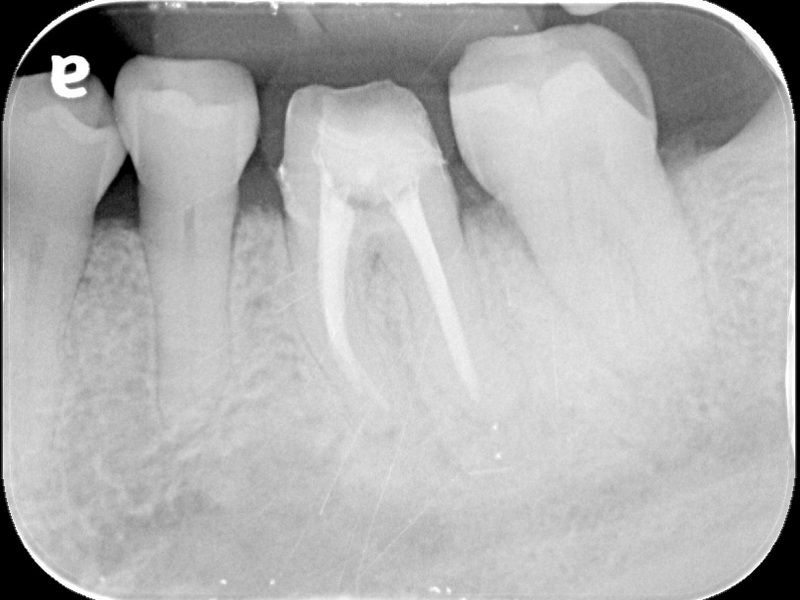

74歲的陳爺爺左下顎第一大臼齒處多年前曾接受根管治療,並裝上牙套,去年年中因為該處長了膿包,出現不適感,在坊間診所拆除舊牙套後,轉診來到台北慈濟醫院牙科部牙髓病科黃耀民醫師門診,希望在不拔牙的情況下解決膿包問題。透過X光及臨床檢查,黃耀民醫師發現膿包位在大臼齒頰側靠後方位置,且牙根底部有黑影表示有發炎狀況,左側根管內亦留存上次根管治療的分離器械。黃耀民醫師在顯微鏡視野下,利用超音波器械將根管內原有的馬來膠針封填物及分離器械移除,並徹底清潔根管系統,最後做緊密的封填。半年後回診,陳爺爺無任何不適,牙根尖的發炎狀況已經消失,膿包也未再出現,便返回原診所重做牙套。

根管治療是將根管系統做徹底的清創,藉由治療器械及殺菌藥水移除所有的牙髓組織及感染原,最後再用根管封填材料做緻密的充填,以維持清潔環境並減少病菌再次入侵感染的機會。黃耀民醫師提到,根管治療是為了增加保留牙齒的機會避免被拔除,但因為操作範圍狹小,且根管型態複雜多變,且可能還有根管彎曲、鈣化阻塞等現象,過去只能倚靠醫師臨床經驗及手感進行治療,容易有清創程度不足而導致治療效果不佳的現象。而牙科顯微鏡是現今輔助治療的新趨勢,可提供充分的照明及最大25至30的放大倍率,讓醫師更能看清楚根管系統,再搭配超音波器械,以最少破壞齒質的方式,做最大程度的清潔。一般而言,傳統根管治療的成功率約7至8成,而顯微鏡輔助根管治療的成功率可高達9成。